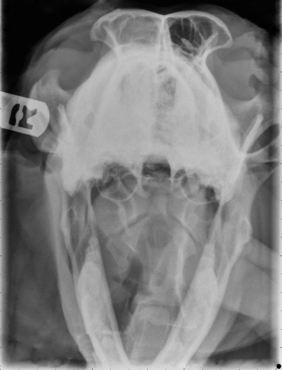

Radiography

Radiographic imaging or CT is always performed before rhinoscopy. Rhinoscopic iatrogenic hemorrhaging and irrigation fluid used during the procedure will distort tissue and create fluid densities that can influence the findings in any radiographic study. Nasal radiographs can be performed in most hospitals and, with practice, can be very useful in the localization and characterization of nasal and nasopharyngeal disease.5 Nasal radiographs require general anesthesia and special patient positioning. Most commonly performed are 30-degree beam-angled open-mouth ventrodorsal and straight lateral views. The open-mouth view provides a complete, symmetrical image of the nasal cavity without superimposition of the mandible. Tumors typically show asymmetrical opacities and turbinate destruction (Figure 19-6). Turbinate destruction is also seen with fungal rhinitis. The straight lateral view allows evaluation of the nasopharynx and frontal sinuses (Figure 19-7). Further study of the frontal sinuses is achieved with a rostrocaudal tangential view (Figure 19-8). This allows comparison of the left and right frontal sinuses as the cavities are superimposed on the lateral view. Dental films of the maxillary arcade are sometimes needed to rule out tooth root abscesses and oronasal fistulae. MRI and CT scans are becoming more commonly available and provide better detail of the nasal, nasopharyngeal, and sinus cavities and cranial vault anatomy compared with standard radiography.6,7 Advanced imaging via MRI and CT, although considered state of the art, assist in description and localization of diseased tissue but have not yet produced results specific enough to eliminate the need for rhinoscopy8,9 (Figures 19-9 through 19-11) (Table 19-1).

image

Figure 19-6 Canine open-mouth ventrodorsal view with right-sided destructive soft tissue mass; nasal osteosarcoma.